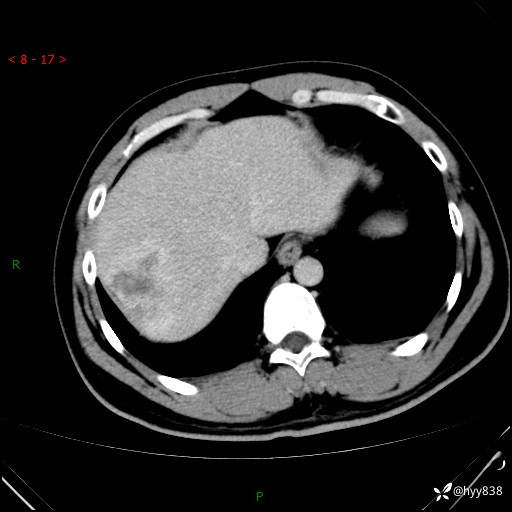

延迟期

img